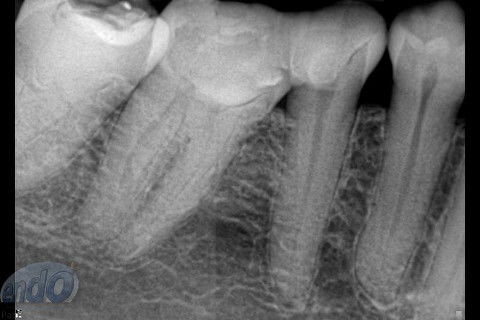

Tratamento Endodôntico dos Dentes 45 - 46 - 47

Seguem 3 casos clínicos realizados esta semana em uma cliente que está passando por um tratamento estético. O dente 47 apresentava calcificação da entradas dos canais radiculares, provavelmente, devido a uma pulpotomia realizada no passado. Desta forma, foi dedicada uma consulta de aproximadamente 2 horas para a realização deste procedimento. Os dente 45 e 46, por apresentarem canais radiculares com menor complexidade, foram tratados, simultaneamente, em sessão única com duração de aproximadamente 2 horas e 15 minutos.

Os três dentes foram tratados seguindo a técnica da FOP-UNICAMP, na qual é realizada patência e ampliação do forame apical. A instrumentação foi realizada com instrumentos rotatórios e como substância química auxiliar foram utilizados o ENDOGEL e o EDTA 17%. A irrigação ativa foi realizada com soro fisiológico. Os canais foram obturados com guta-percha e cimento PulpCanal Sealer, pela técnica de ondas contínuas de condensação.

Os procedimentos pré-restauradores nos dentes 46 e 47 envolveram apenas a confecção de núcleo de preenchimento em resina composta (Z250 B0,5). No dente 45 foi instalado um pino de fibra de vidro (FGM) e confeccionado núcleo de preenchimento em resina composta (Z250 B0,5).